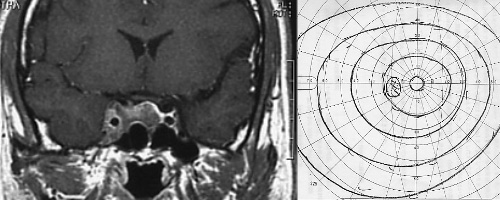

残存、増大下垂体腺腫 視野欠損 5分割で治療

11ヵ月 後視野欠損改善

46ヵ月後 腫瘍の著名な縮小